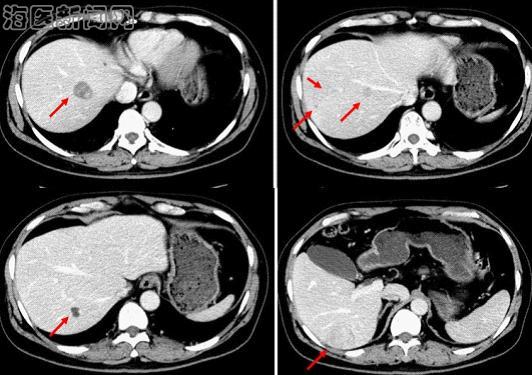

该名患者为老年男性,肝脏CT检查示6、7、8段出现多发占位,考虑原发性肝癌。但病人的体重较重,左半肝体积又很小,如行右半肝切除左半肝不能满足病人所需的最小肝脏体积,术后发生肝功能衰竭的风险极高。该病例的病灶位于右肝6、7、8段,若能保留5段则剩余肝脏能满足病人所需的最小肝脏体积,因此经过严密的术前讨论分析,肝胆外科贾长库主任选择了手术难度非常大的保留5段的规则性右肝三段切除。

据了解,这种规则性肝段切除的难度极大,既要明确各段的具体位置,又要保证保留的肝段有良好的血供和回流。手术中成功解剖第一肝门,尤其是分别解剖出右半肝和6、7段的格林森氏蒂,从而确定和标记8段与左肝的分界线,以及确定和标记出6段与5段之间的分界线尤为重要,是手术最关键的要点。通过这样的两次标记后可以确定出预保留的5段位置。从而在肝脏的脏面上确定出类似于“

”型的切除线。

此外,5段肝脏由肝中静脉引流,因此术中避免损伤肝中静脉从而保证保留的5段有良好的回流非常重要,是手术的第二个难点和要点。另外,本例手术采用选择性肝脏血流阻断技术,在切割横断6段和5段以及5段和8段之间的肝实质时只阻断右半肝的入肝血流,在切割横断8段和左肝之间的肝实质时才阻断全肝的入肝血流,最大程度的减少肝脏的缺血再灌注损伤。肝硬化患者在手术中对缺血和失血的耐受性差,不能经受长时间的全肝入肝血流阻断,选择性肝脏血流阻断技术保证切肝时健侧肝脏正常的血供,又可使肠系膜血流通过健侧肝脏回流,不仅有利于血液动力学的稳定,也不会发生因肝门阻断造成的细菌及内毒素移位和肠粘膜的损伤,对本例病人的顺利完成手术及术后恢复都至关重要。完成肝切除后保留的5段及左肝血供及回流均很好。